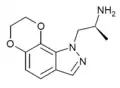

MPMI[26] | 3-[(1-methylpyrrolidin-2-yl)methyl]-1H-indole | 143321-54-4 |

|